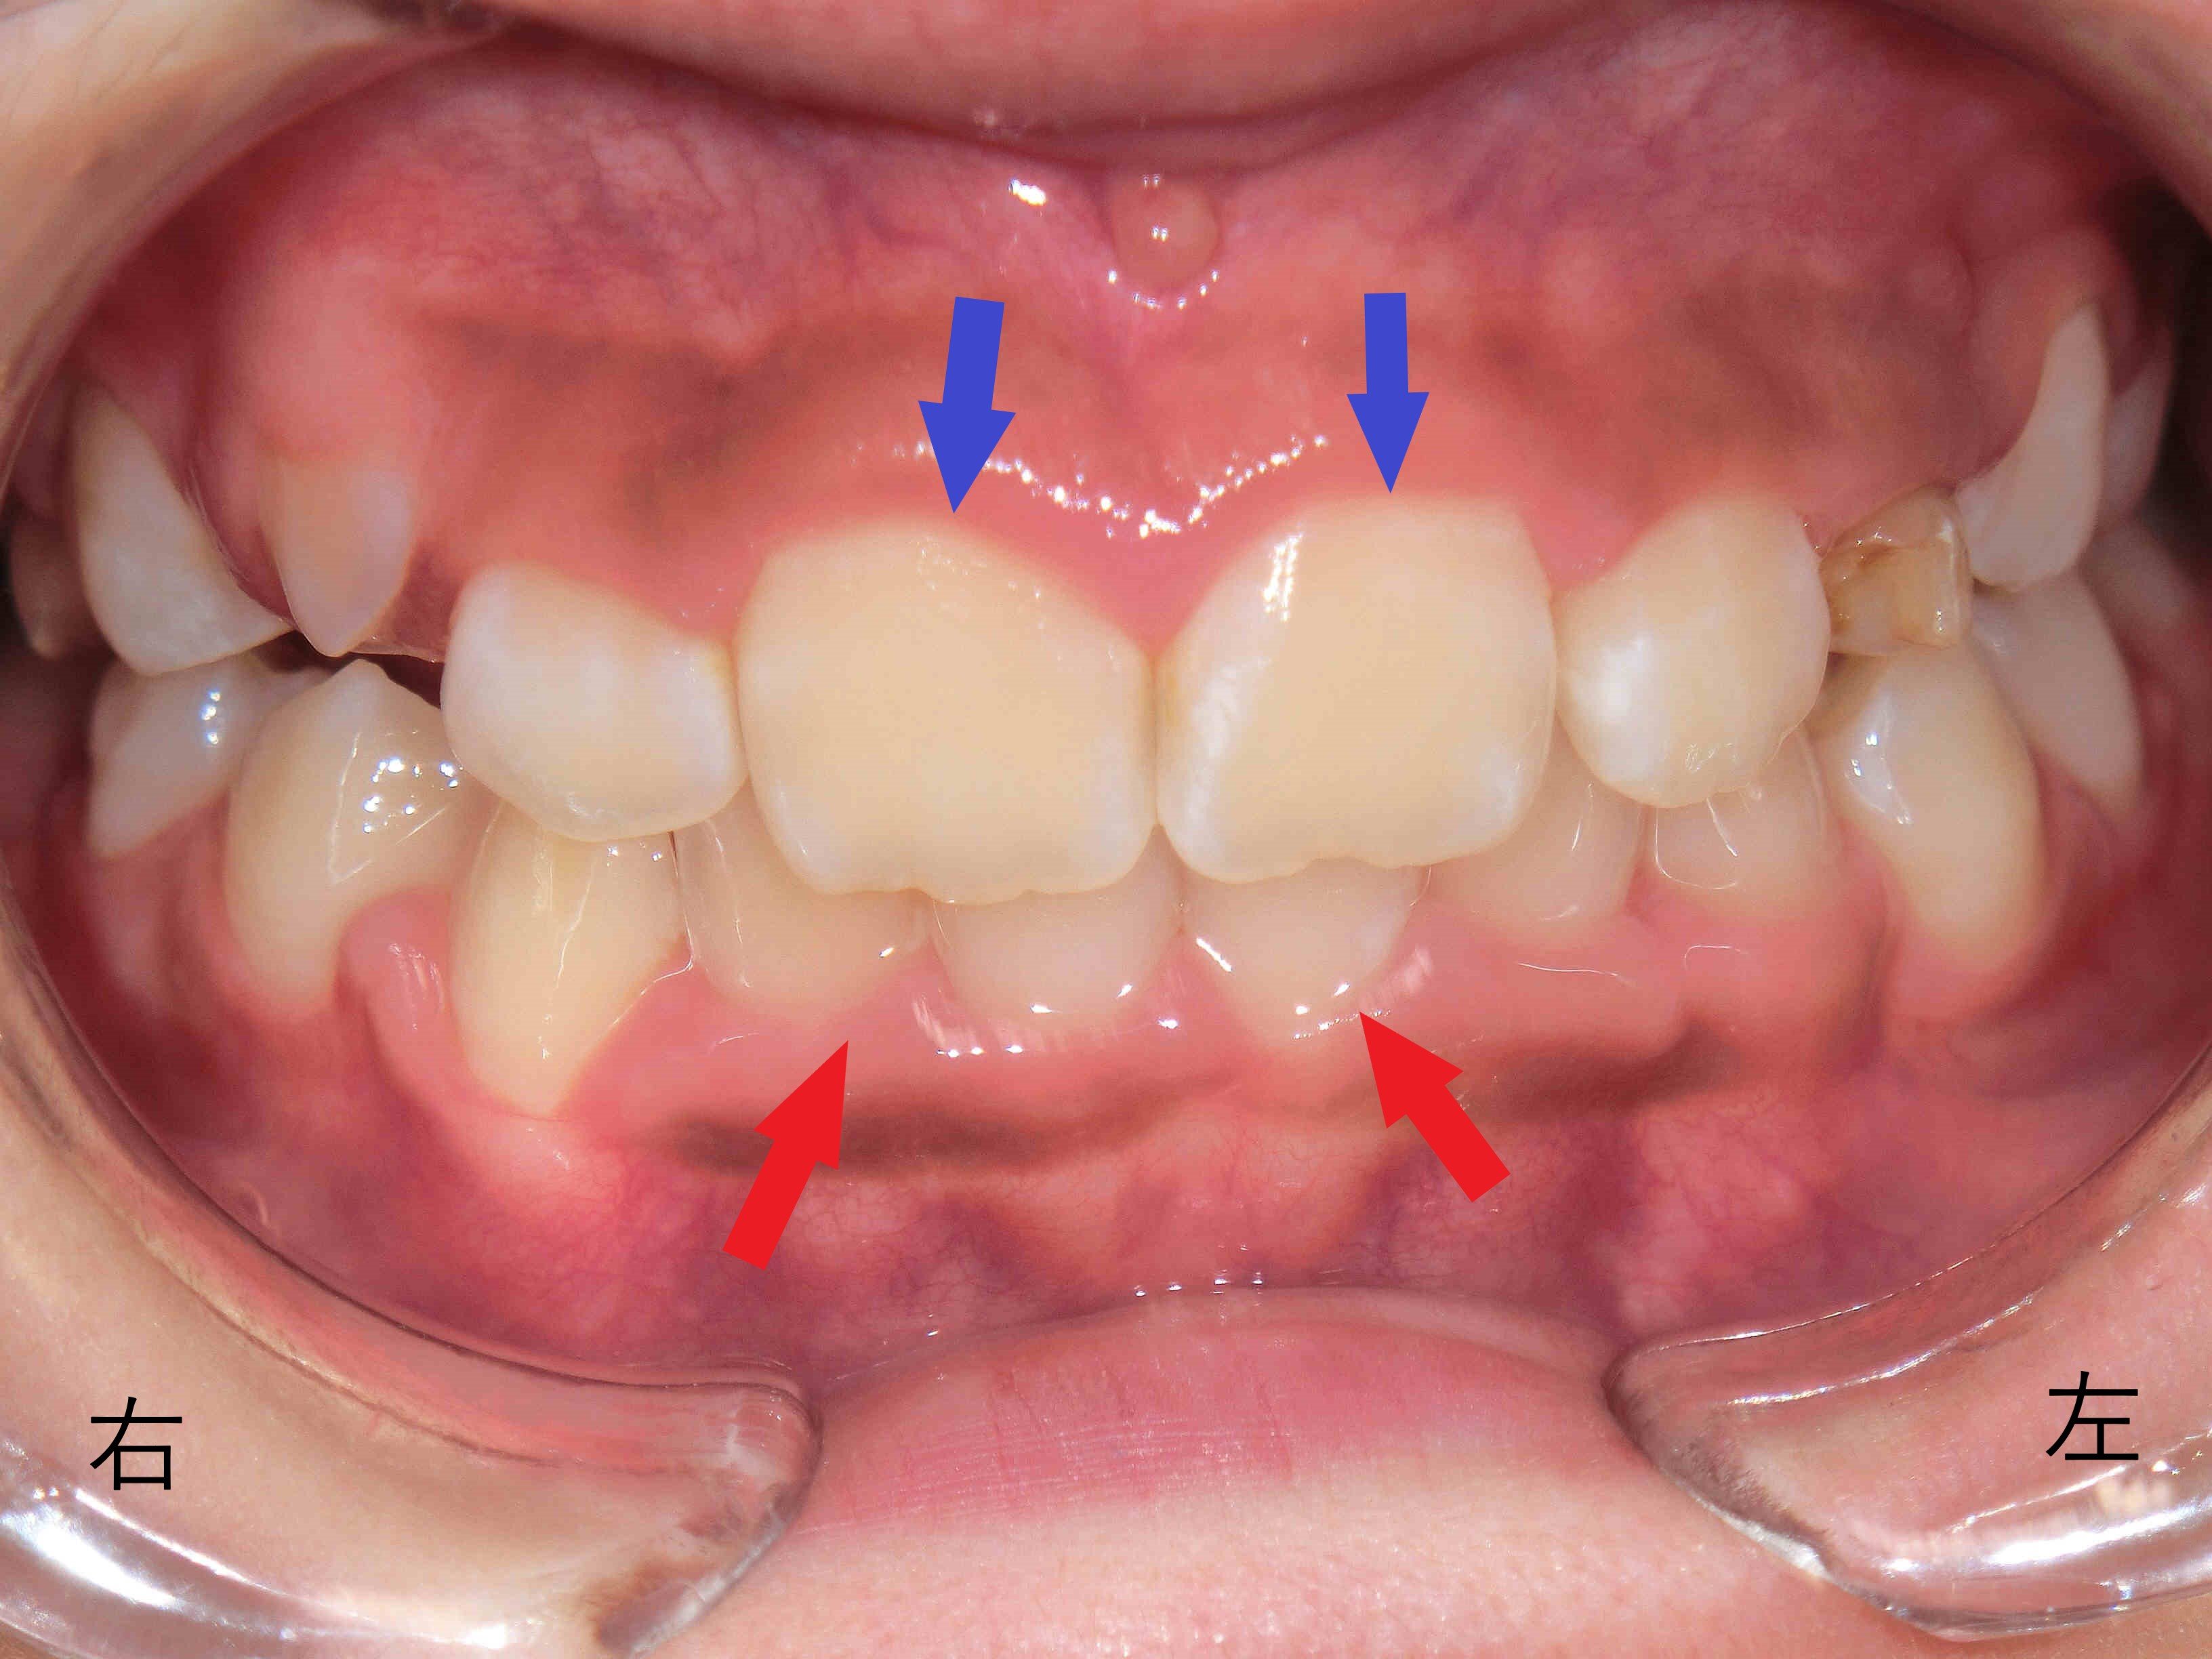

こちらは、マイオブレイスなどの取り外し式矯正装置を用いた小児矯正治療の症例です。治療開始から6か月後の前歯の噛み合わせを撮影した写真をご覧ください。

赤色矢印で示した下顎前歯が、上顎前歯(青色矢印)に隠れていた状態から、下顎の前方成長により前方から見えるようになってきています。